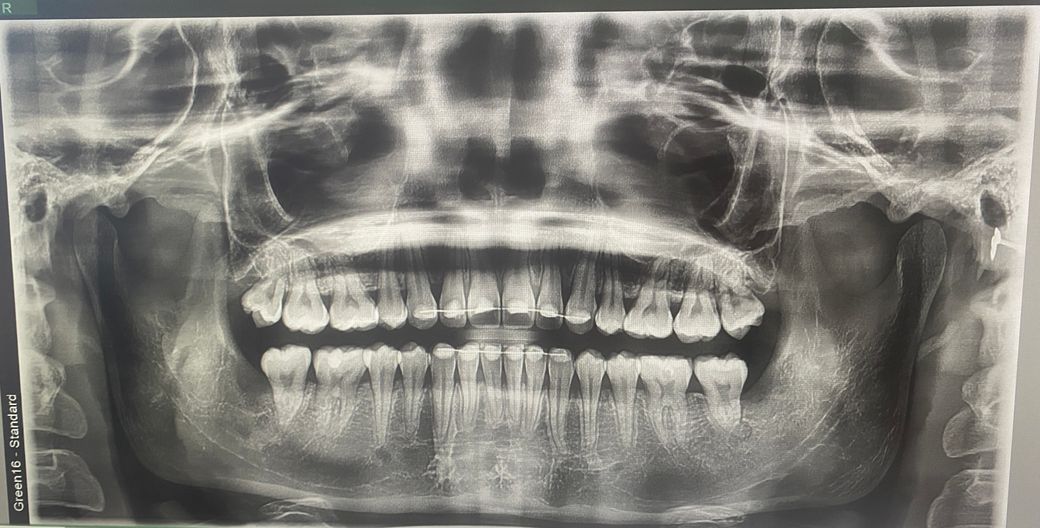

턱관절 엑스레이 상 과두 위치에 문제가 있을까요?

제 턱관절 엑스레이인데 엑스레이만 봤을 때 문제가 있어보이나요? 과두 위치가 정상적인지, 관절염이나 다른 이상소견이 있는지 궁금합니다

• 1번 째 사진

엑스레이 상으로 보면 턱관절 연골이 닳아잇는것처럼 보입니다. 통증이 잇거나 불편하시면 치과를 다니시면서 치료를 받아보시는게 좋을것같습니다.

과두위치 이상이나 관절염이 현재 올려주신 엑스레이 에서는 특정되어 나타나진 않습니다.

파노라마 사진상으로는 정확한 과두의 위치나 형태를 진단하기 어렵습니다.

턱관절 질환의 유무나 형태은 주로 증상이나 CT상으로 확인을 할수 있습니다.